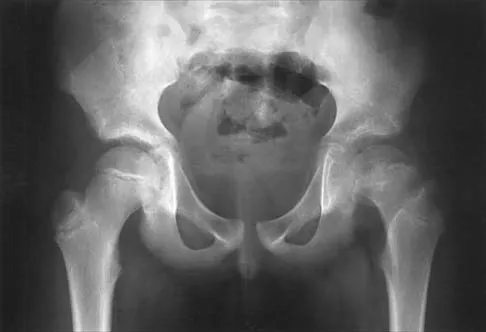

Figures 39a and 39b show the radiographs of an otherwise healthy 10-year-old boy who has had thigh pain and a limp for the past 9 months. Examination reveals that the left lower extremity is 1 cm shorter, with reduced flexion, abduction, and internal rotation on the left side. The patient is at the 50th percentile for height and the 90th percentile for weight. Serum studies will most likely show

Explanation

The patient has a slipped capital femoral epiphysis (SCFE) at a younger than average age (average age 13.5 years for boys and 12.0 years for girls); therefore, an etiology that is not idiopathic must be considered. Hypothyroidism can result in a SCFE, but these children typically fall into the category of less than the 10th percentile for height. SCFE may develop in children with a growth hormone deficiency who have undergone hormonal replacement. Osteodystrophy caused by chronic renal failure may result in a SCFE, but the bone quality is markedly osteopenic on radiographs and the children are chronically ill with both low height and weight percentiles. An elevated estrogen level results in physeal closure and is protective to physeal slippage. Therefore, this child will most likely have normal laboratory values. Loder RT, Hensinger RN: Slipped capital femoral epiphysis associated with renal failure osteodystrophy. J Pediatr Orthop 1997;17:205-211.